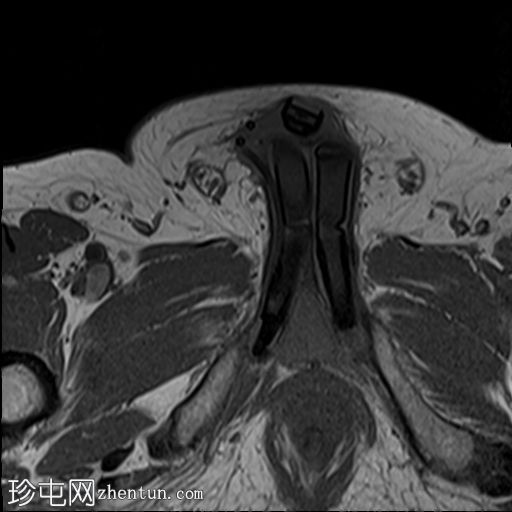

轴位

T2加权像

MRI显示可充气式阴茎假体位于体内。

假体柱体对称地位于阴茎海绵体内,并沿其走行方向完全扩张。

未见海绵体破裂或假体柱体断裂的迹象。

泵储液囊位于阴囊内,位置正常。

阴囊壁皮下可见轻度水肿,但无明显积液,可能为反应性水肿。

储液囊位于右侧腹股沟管前方的皮下脂肪内,对右侧腹直肌施加轻微的向上压迫,周围有少量积液。这些发现最符合术后改变。

在本病例中,MRI显示假体圆柱体位置正常,无破裂或不连续的迹象。储液囊和泵的位置也正确。周围轻微的水肿和积液可能是术后改变。因此,患者的症状可能与机械刺激或装置相关的机械因素有关,而不是假体的结构性故障。